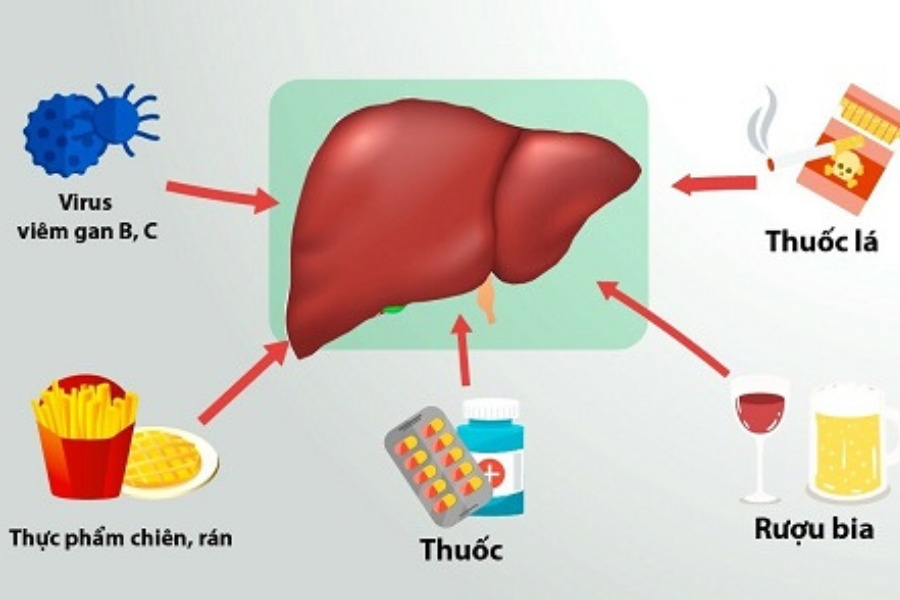

Có nhiều nguyên nhân phổ biến khiến gan bị quá tải:

– Lối sống và chế độ ăn uống: Thường xuyên uống rượu bia là nguyên nhân hàng đầu gây ngộ độc và phá hủy trực tiếp tế bào gan. Bên cạnh đó, tình trạng béo phì và bệnh gan nhiễm mỡ (đặc biệt là gan nhiễm mỡ không do rượu) cũng khiến gan bị quá tải.

– Sử dụng thuốc và nhiễm độc tố: Lạm dụng các loại thuốc không kê đơn như thuốc giảm đau (đặc biệt là paracetamol/acetaminophen) hoặc thuốc hạ mỡ máu (statin) có thể gây tổn thương gan. Tự ý dùng các loại thực phẩm chức năng, thảo dược không rõ nguồn gốc cũng tạo gánh nặng lớn cho gan.

– Bệnh lý về gan: Nhiễm virus viêm gan A, B, C có thể dẫn đến các bệnh lý truyền nhiễm mạn tính phá hủy gan âm thầm theo thời gian. Các bệnh lý như viêm gan tự miễn, bệnh Wilson (rối loạn tích tụ đồng), hay rối loạn ứ sắt (Hemochromatosis) cũng là những nguyên nhân thường gặp khiến men gan tăng cao.

Các nguyên nhân gây tăng men gan.